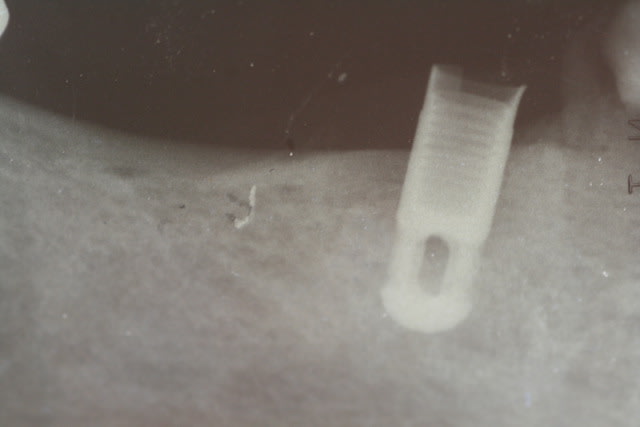

quelqu'un reconnait'il cet implant pose il y a plus de 30 ans!Ci-joint radio de l'implant et photo de la vis de couverture.Merci pour votre aide.

A la radio ça fait penser à un vieil IMZ du Dr Kirsche

+1 on dirait bien un IMZ...